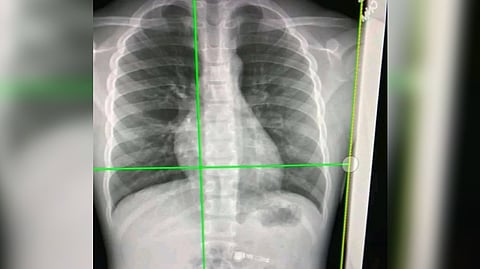

NEW YORK: For patients dealing with lingering respiratory symptoms from the coronavirus, a simple chest X-ray can now reveal its impact on the lungs.

The two-dimensional (2D) scans simply can't distinguish compromised lung function and a more expensive CT scan is necessary.